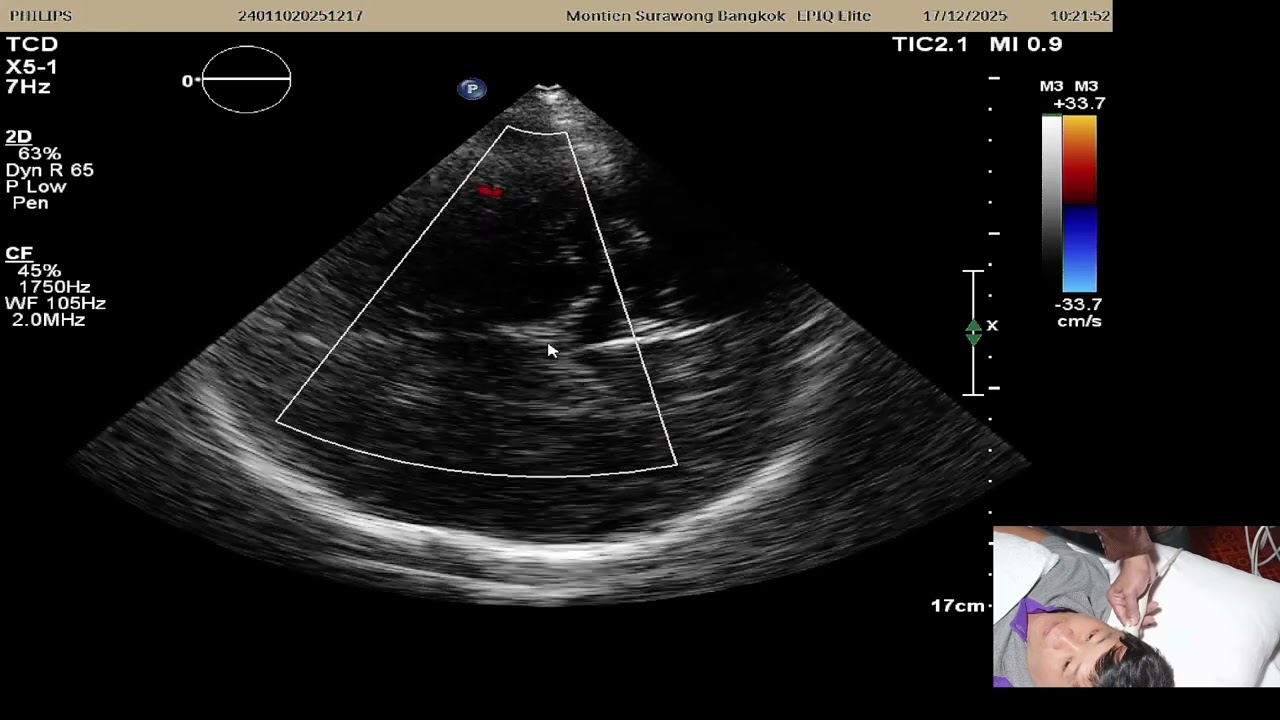

วิธีทำ Apical Four Chamber เพื่อดูหัวใจสี่ห้อง

นอกจาก Subxyphoid ก็มี Apical four chamber นี้แหละ

ที่เห็น RA

เทียบ RV กับ LV ได้

เห็น Pericardial Effusion แม้ loculated หลัง ผ่าตัด

เห็น EF ในแนวยาว

และบางครั้งเห็น LV aneurysm